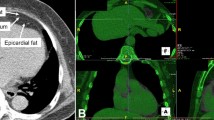

Perivascular fat analysis

PCAT was extracted automatically by using the Skviewer software FAI intelligent analysis system (Skviewer FAI; Shukun Technology, Beijing, China) [12]. The volume and FAI of PCAT were measured using the method described by Oikonomou et al. [7]; the threshold value of PCAT ranged from − 190 to − 30 HU, the measured length was 40 mm, and the extracted radial distance was the average diameter of the target vessel. The segment analyzed was the proximal 40 mm of the left anterior descending (LAD) and left circumflex (LCX) arteries and the proximal 10–50 mm of the right coronary artery (RCA). The software could extract PACT volume and FAI automatically, and when the automatic extraction was inaccurate, we adjusted the extraction range manually. Subsequently, the PCAT volume and FAI were calculated by the software automatically (Fig. 2). The above measurement results were completed by an experienced radiologist independently. In order to test the consistency of the measurement results, 20% (32) of patients were randomly selected 1 month later, and a second measurement session was carried out by 2 radiologists. An intraobserver consistency test was carried out on the results measured by the same doctor, and an interobserver consistency test was carried out on the results measured by 2 doctors (Additional file 1).

Some studies on the correlation between epicardial fat volume (EFV) and CAD reported that the increase of EFV was positively correlated with the risk of CAD [16, 17]. Severe CAD often leads to changes in cardiac function, and studies have shown that there is a correlation between EVF and LV function parameters [18, 19]. Thus, we analyzed the relationship between PCAT volume, Gensini score, and LV function parameters and found that there was no correlation between them. The possible reason for this is that the measurement methods are different. The extraction range of EFV is all adipose tissue from the aortic root to the apex of the heart, and the radial range of extraction of PCAT is equal to the diameter of the target vessel. Many factors are related to coronary heart disease, including obesity, diabetes, and hypertension [20, 21]. Previous studies have shown that EVF is correlated with traditional risk factors of coronary heart disease [22,23,24] and positively correlated with BMI [25]. However, some research results suggest that EVF can be an independent predictor of CAD [26] and is not associated with the traditional risk factors of CAD [27, 28]. Therefore, we analyzed the correlation between PCAT volume, BMI, and risk factors for CAD. Our results showed that PCAT volume did not correlate with BMI or risk factors for coronary heart disease. These differences in results may be related to different measurement methods, pathological changes in the natural course of the disease, lifestyle factors, and drug intervention [29, 30]. Our results showed that only the results of LCX and total volumes were statistically significant (P < 0.05). This may be related to the reduced amount of adipose tissue around the LCX; the method we adopted can cover a more complete vessel volume. The correlation shown with the total volume may be affected by LCX. In a study of pericoronary epicardial adipose tissue by Vos et al. [31], only the fat volume around LCX showed different results from LAD and RCA, which was similar to our results. Inflammation is a critical factor not only for the development but also the progression of atherosclerosis [1, 32, 33]. Inflammatory factors released by the arterial wall can induce lipolysis, inhibit lipogenesis, and promote perivascular edema [34]. Meanwhile, the cytokines secreted by adipose tissue play a significant role in atherogenesis and myocardial ischemia [35, 36]. These changes showed attenuation from lipids (close to − 190 Hu) to water (close to − 30 Hu) on CT [37, 38]. Therefore, coronary inflammation can be detected by FAI.